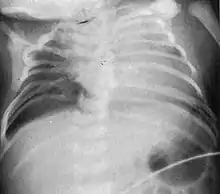

| Radiograph depicting typical skeletal features of Jarcho-Levin syndrome, subtype spondylothoracic dysplasia. Note fanlike configuration of the ribs, with extensive posterior fusion, along with multiple vertebral segmentation defects. | |

Spondylothoracic dysplasia

Spondylothoracic dysplasia, or STD, has been repeatedly described as an autosomal recessively inherited condition that results in a characteristic fan-like configuration of the ribs with minimal intrinsic rib anomalies. Infants born with this condition typically died early in life due to recurrent respiratory infections and pneumonia due to their restricted thorax.[3][4][5] Recently, a report[6] has documented that actual mortality associated with STD is only about 50%, with many survivors leading healthy, independent lives.